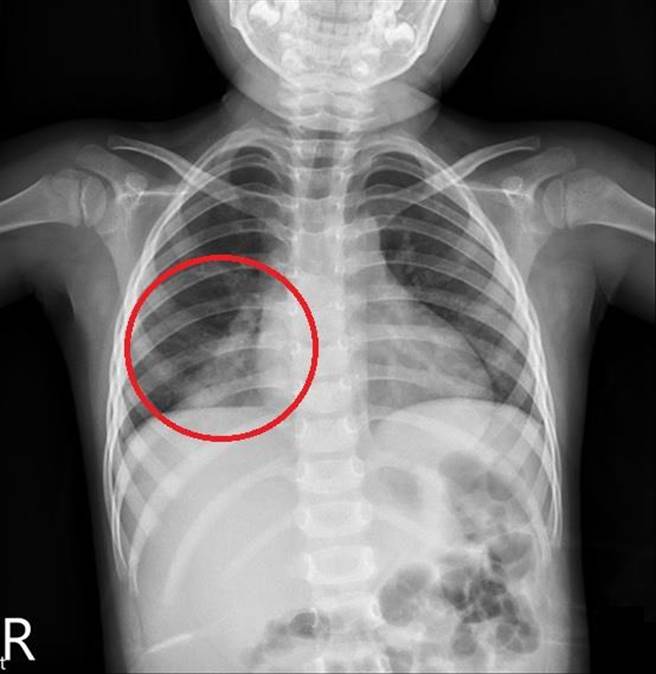

台中3岁女童连续5天高烧40度不退,医师排除新冠病毒、A型流感、霉浆菌及肠病毒等常见疾病后,检查发现为肺炎链球菌,幸给予抗生素治疗后顺利退烧、大幅好转。(亚大附医提供/潘虹恩台中传真)

他说明,患者没有明显咳嗽,经安排X光检查发现女童右下肺叶明显肺炎,再送「尿液肺炎链球菌快速抗原检验」呈阳性,证实为肺炎链球菌引发右下肺炎,幸经抗生素治疗24小时内即退烧,精神及食欲也恢復正常。